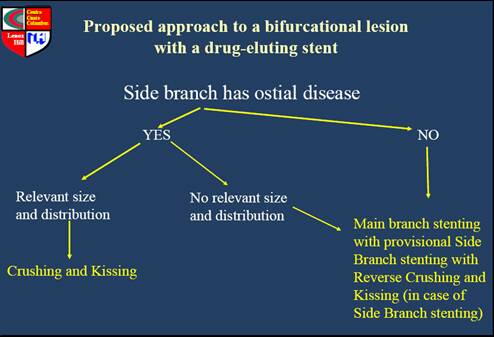

�o�b�q��bifurcation�̃Z�b�V�����ŃR�����{���������Ǘ�́A�z���J���ɃX�e���g��

�āAKBT�����āA���߂Ȃ�A���}�ɃX�e���g���āA������z���J���̃o���[������āA

�N���b�V�����āA�Ō��final KBT�Ŏ������Âł����B

����X���C�h�ł��A�R�����{���A���ɑ��ẮAprovisional�Ƀz���J�����X�e��

�g���āA���߂Ȃ�Areverse crush stenting������Ƃ������������Ă���̂ŁA�����A

�����搶�̒�`�ł́A�����Ǝv���܂��B

�����搶�̒�`�́A�z���J���A���}�Ƃ����̋t�ł����A�X�e���g���ɂ���Ă�����

���Ƃ����Ȃ��̂ŁAprovisinal�ɂ͂ł��܂���A��͂肻�̎�Z�̓N���b�V���Ƃ�

���̂ł͂Ȃ��ł��傤���H

�R�����{���D�������Ăɂ����Ă��@�ł�����A�ǂ��Œ�`������邩�킩��܂���

���A�l�͂��̕��@�����Ƃ��ɂ́ADES�Ȃ�ł́A���@�Ȃ̂ŁA�������܂����B